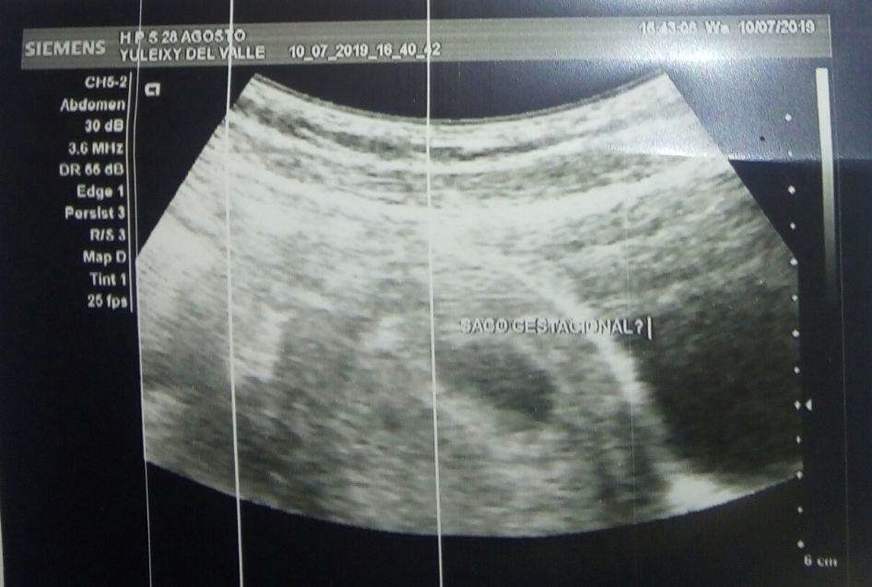

De acordo com o pai da venezuelana, o exame que comprovou a gravidez foi feito no Hospital 28 de Agosto na terça-feira (9). Ele acredita que o padre acusado pela filha de estupro é o pai da criança.